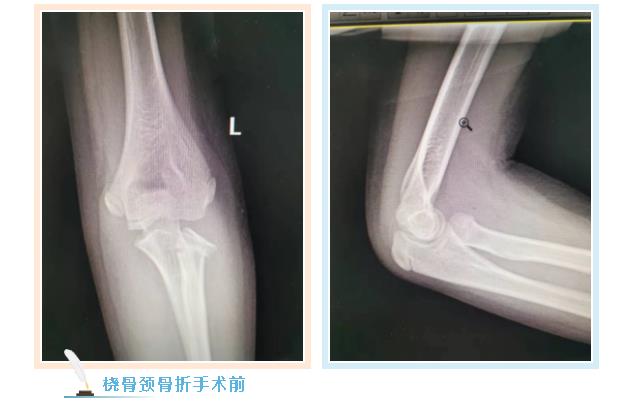

887700线路检测网骨伤二科副主任张永青仔细查看孩子患处,安排其进行放射拍片检查,结果为左侧桡骨颈骨折,根据孩子的骨折状况,张主任认为保守治疗很难做到理想复位,且复位后较难维持良好位置,可能会影响将来前臂的旋转功能,建议孩子尽快接受手术治疗,孩子的家长担心传统手术切口大,孩子所受痛苦多,犹豫不决,张主任与家长沟通,孩子要接受的不是传统的开放手术,而是“骨折闭合复位弹性髓内钉内固定”微创手术,手术只需要一个0.5-1厘米左右的切口就可以达到满意的效果,家长立即同意接受手术治疗。手术非常成功,术后第三天,周周出院。